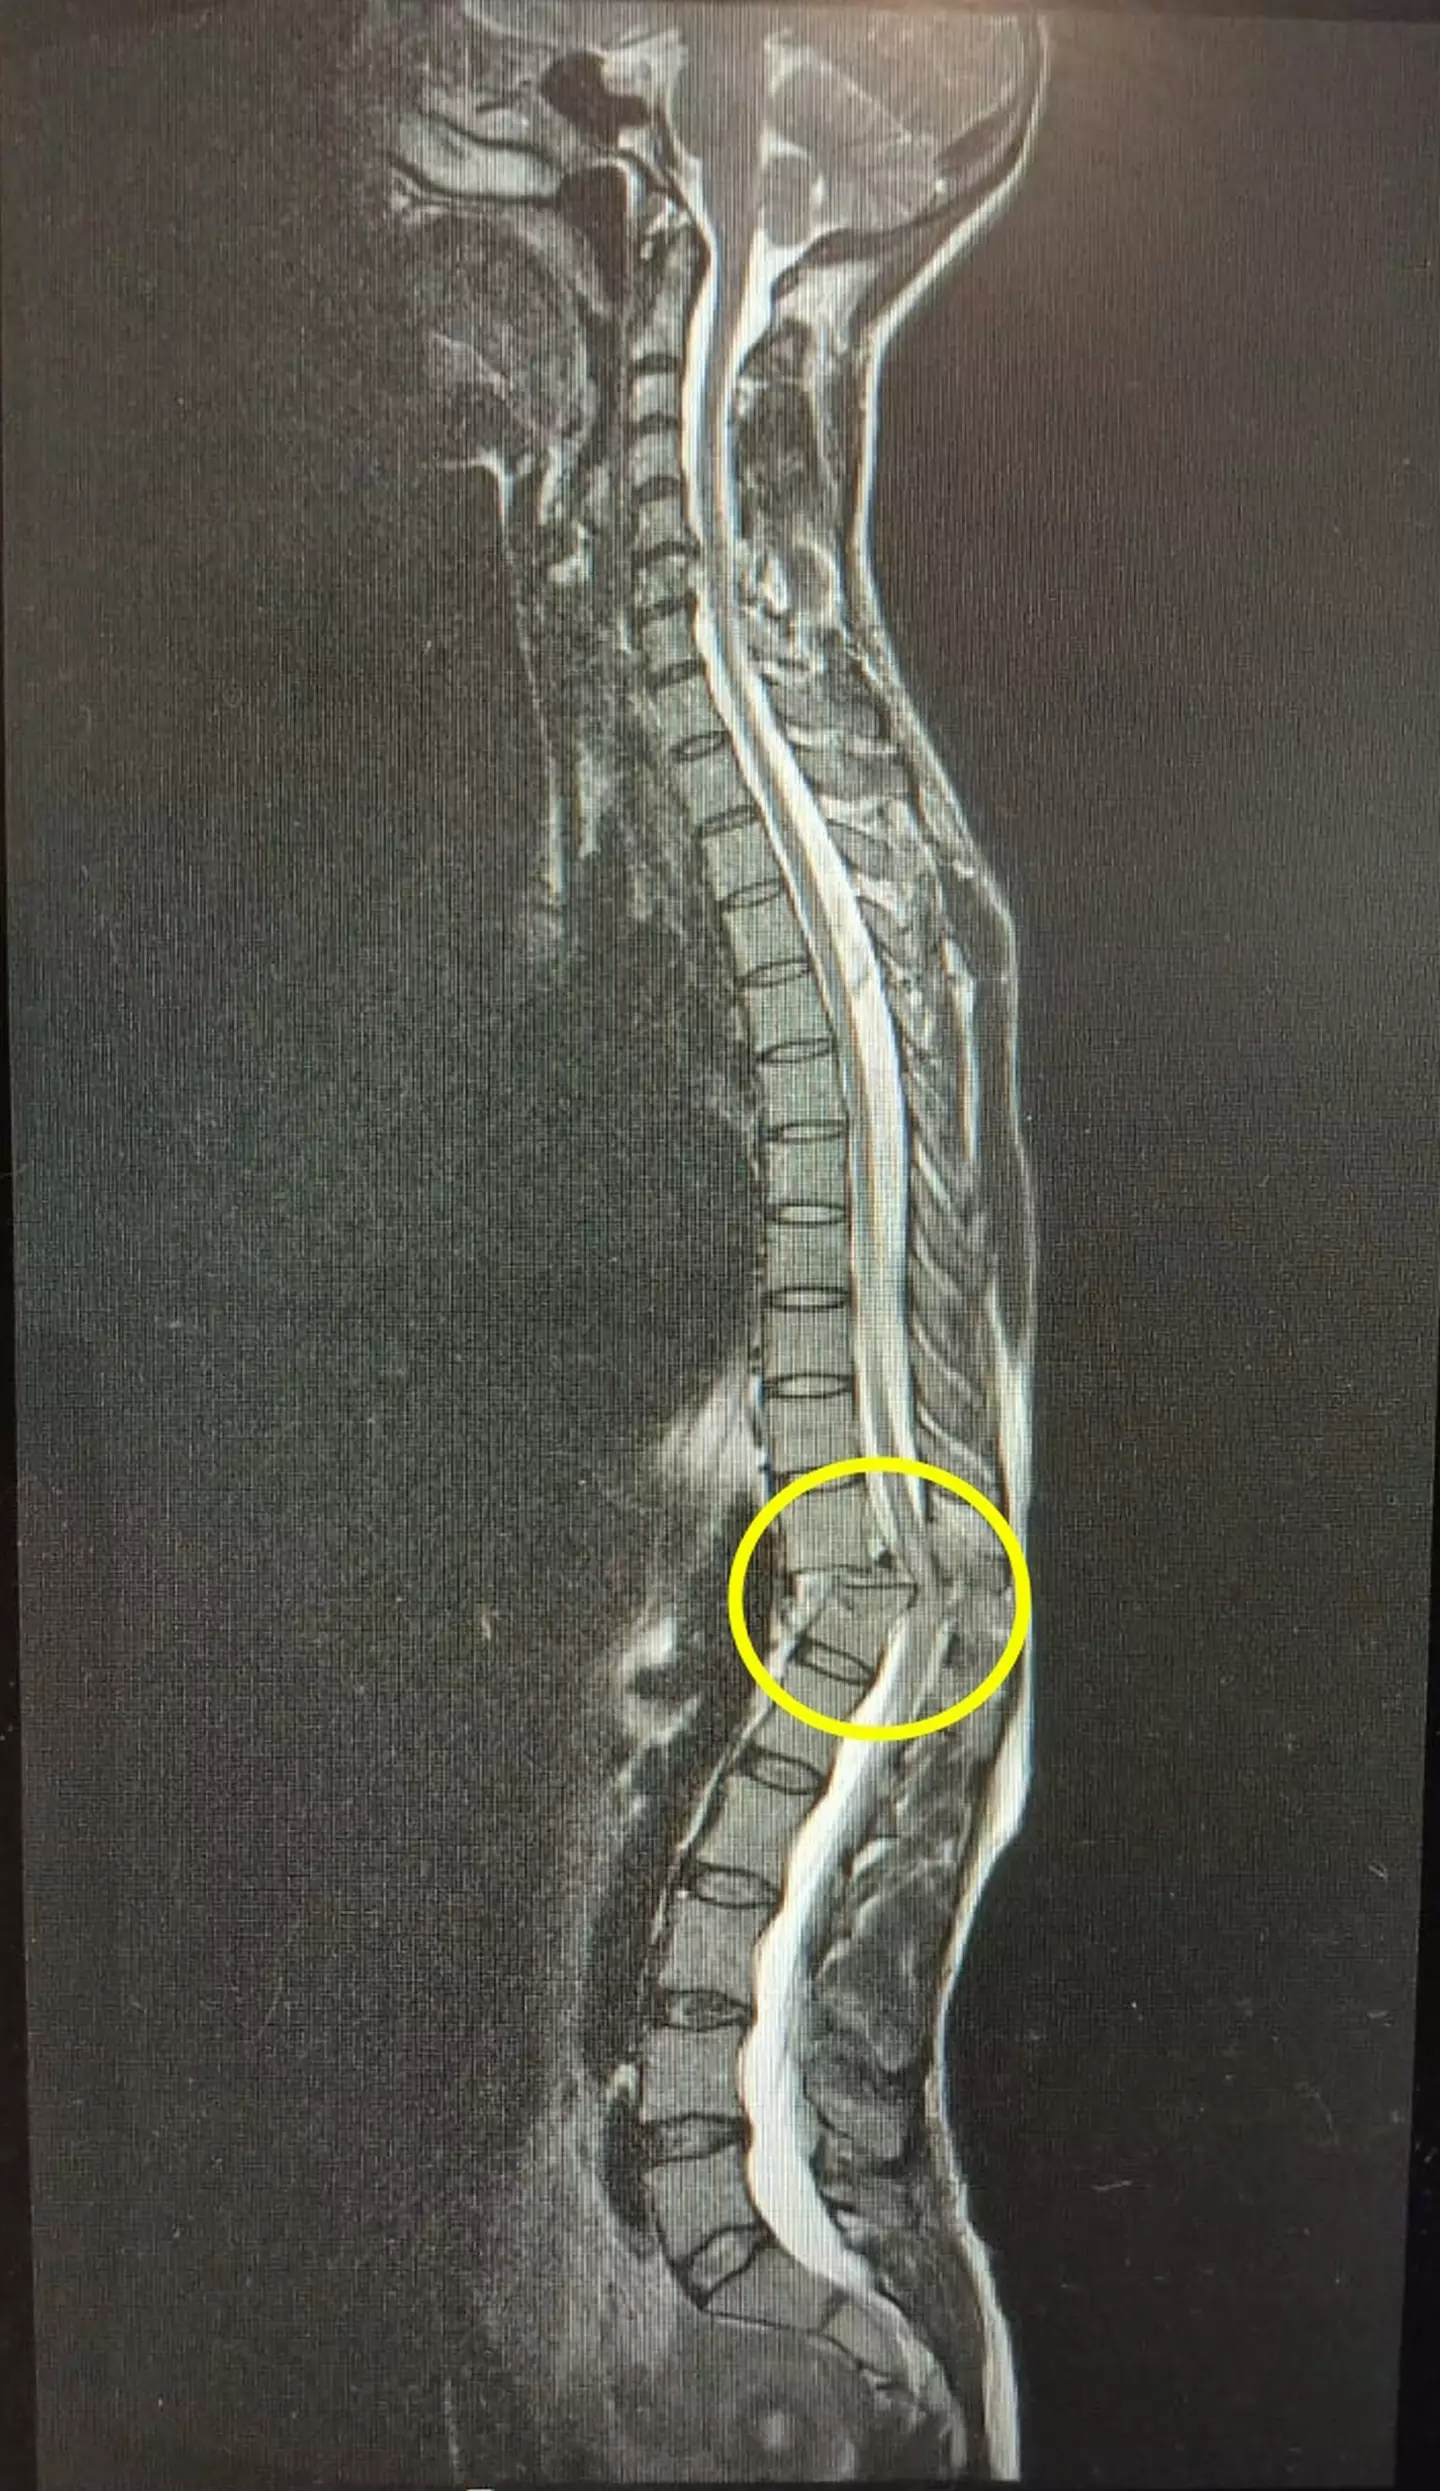

The 40-year-old was in the gym when she was crushed by a weight, and following MRI and CT scans at Southampton General Hospital, she was told by health professionals that she had broken and dislocated parts of her spine, suffering a complete spinal cord injury, paralysing her from the waist down.

She was told it's rare for people to regain feeling in the spine after this type of injury, with the mum-of-two undergoing a procedure the following day to bolt five of her vertebrae together to stabilise her spine.

"The surgery wasn't what worried me as much as just the damage I'd done to my spinal cord which they can't do anything about that. The surgery is just to fix the bone," she explained.